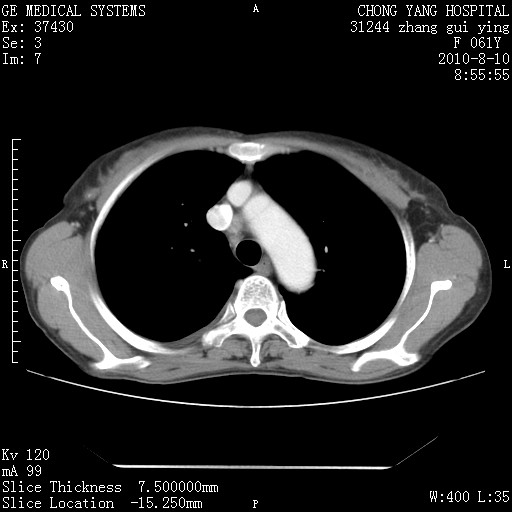

标题: CT28314:F61Y胸部增强,发热咳嗽一周入院,后面的为一周前平

1、支持考虑右侧中央型肺癌伴右肺中叶节段性不张及下叶支气管黏液痰栓    2、左肺上叶舌段感染。

支持3楼意见,还要考虑:纵隔及肺门淋巴结转移、右侧少量胸腔积液。

确切的说:1:右肺下叶中心型肺癌侵及中叶支气管并中叶不张,纵膈淋巴结转移。2:左肺舌叶炎症。3:右侧胸腔少量积液

块影平扫32hu,动静脉期62-70hu.

考虑右下肺肺癌,纵隔淋巴结转移i。